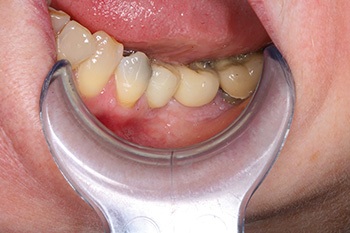

Fig. 6: Restoration view.

Fig. 7: Restoration view in occlusion.

Well, Frances moved to the other side of the country, but I used to see her initially once a year and then every two years, free of charge, just so I could post updates of the case to Dentaltown. As you can see from the most current X-rays, not only has the implant survived, but the bone around the implant (what many worried would be overloaded and lost) looks even better in 2024 than it did in 2009 when the implant was first restored!